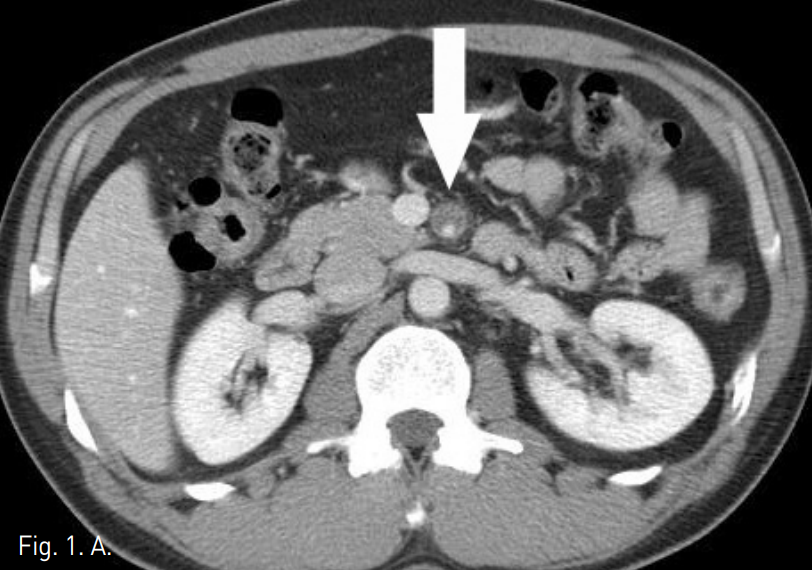

시술 전 CTA상 상장간막동맥 근위부에 직경 10mm 크기의 박리성동맥류가 확인되었고, 상장간막동맥은 벽내혈종으로 인해 혈관 직경은 12mm로 커지고 내강은 3mm로 협착소견을 보였다(Fig. 1A-C).

Fig. 1

A-C. Initial CT scan (A) shows dilated SMA with circumferential intramural hematoma and stenotic true lumen (arrow). Sagittal reconstructed MIP image (B) and volume rendered 3D CTA (C) show 1cm sized dissecting aneurysm (arrow hed) at proximal SMA and diffuse narrowing of true lumen.